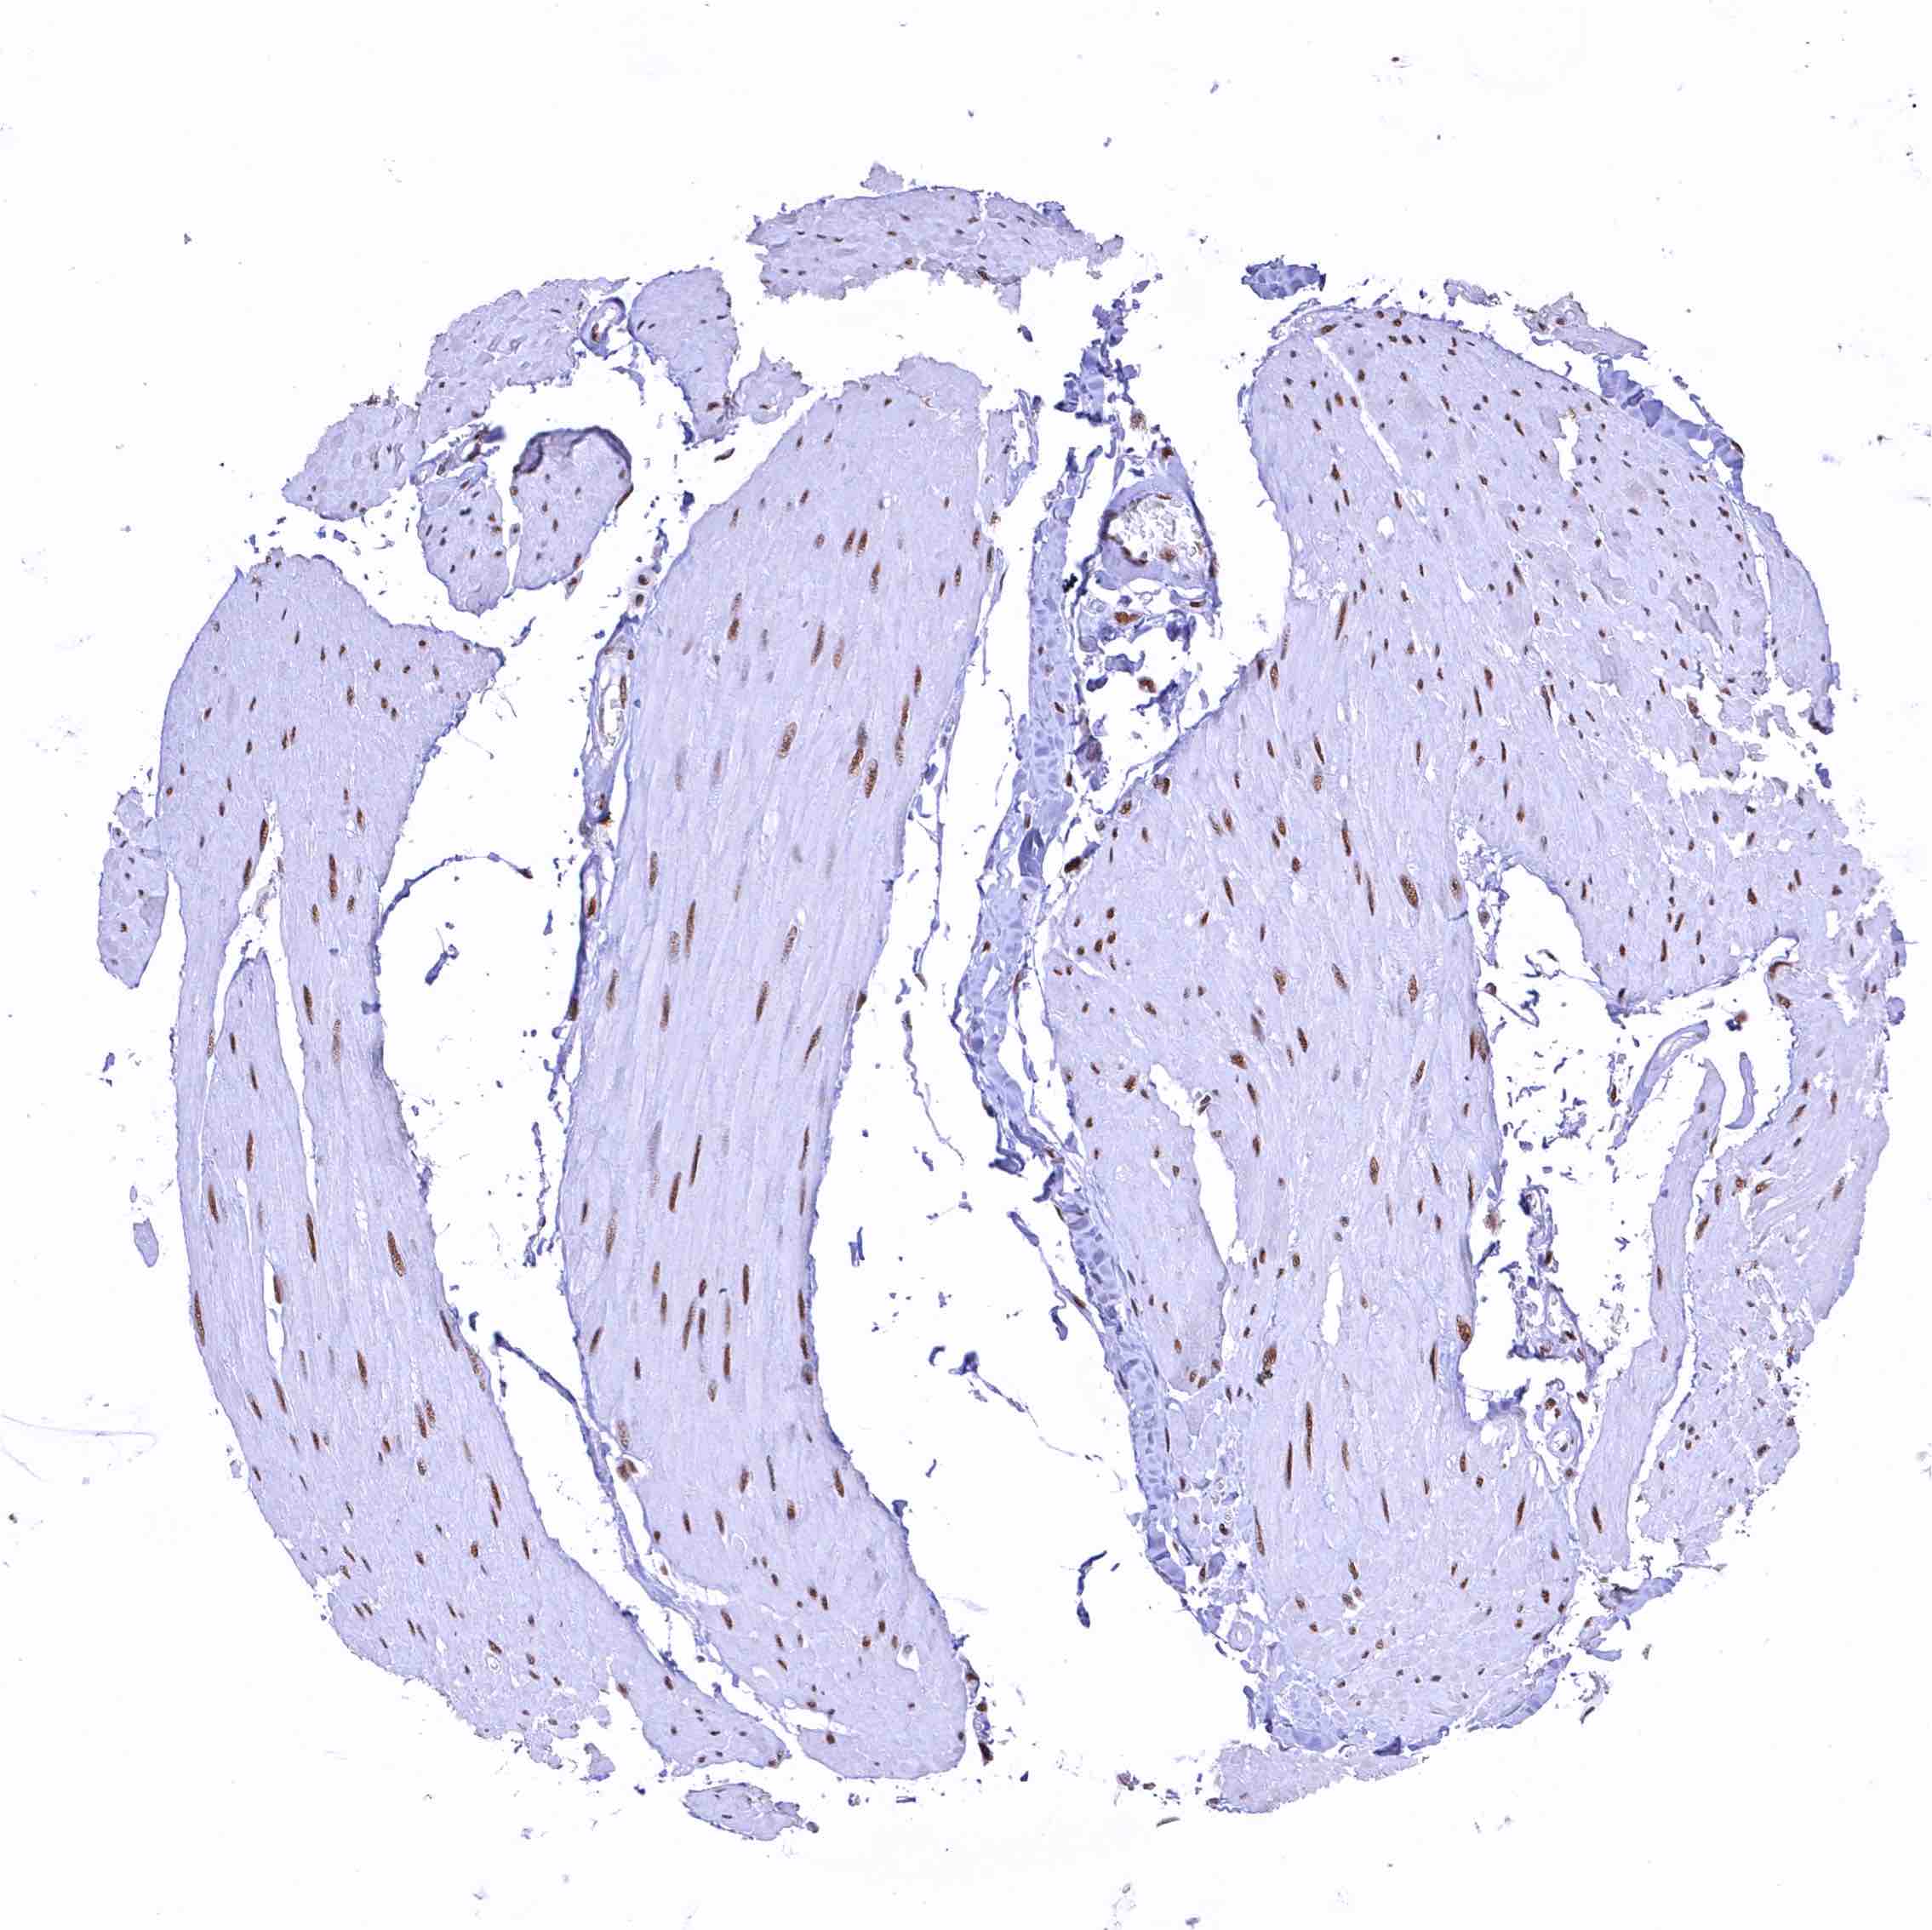

Skeletal muscle